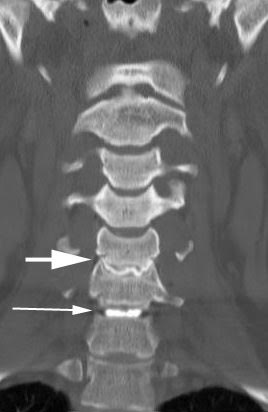

Your doctor will use an imaging technique (fluoroscopy) that enables him or her to watch as the needle enters your body. Fluoroscopy allows more precise and safer placement of the needle into the center of the disk to be examined. A contrast dye is then injected into the disk, and an X-ray or CT scan is taken to see if the dye spreads.

If the dye stays in the center of the disk, the disk is normal. If the dye spreads outside the center of the disk, the disk has undergone some wear-and-tear change. These changes may or may not be the cause of your pain.